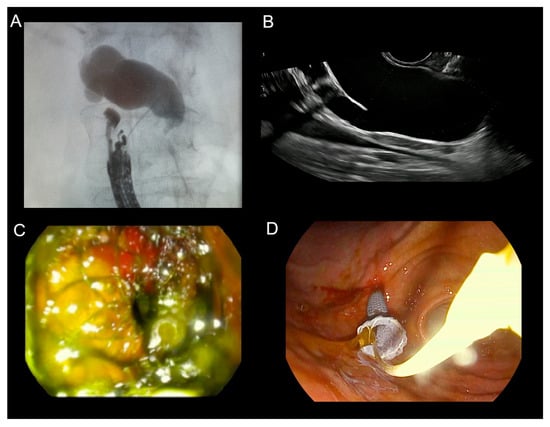

Background: After a failed endoscopic retrograde cholangiopancreatography (ERCP) for malignant biliary obstruction (MBO), second-line drainage is performed with endoscopic ultrasound-guided biliary drainage (EUS-BD) or percutaneous transhepatic biliary drainage (PTBD). We compared their effectiveness, safety, and short-term survival. Methods: We conducted a single-center retrospective cohort of 101 adults with MBO after they had experienced a failed ERCP (EUS-BD n = 37; PTBD n = 64). Allocation was non-randomized and driven by operational availability. Baseline laboratory tests (complete blood count, platelets, and C-reactive protein) and derived indices (neutrophil-to-lymphocyte ratio [NLR], platelet-to-lymphocyte ratio [PLR], lymphocyte-to-monocyte ratio [LMR], systemic immune-inflammation index [SII], systemic inflammation response index [SIRI], neutrophil-to-platelet score [NPS], and lymphocyte-to-CRP ratio [LCR]) were compared. Outcomes that were a technical success include: an early biochemical response (bilirubin reduction), complications (Clavien–Dindo), length of stay (LOS), and overall survival (OS). Between-group comparisons used the two-sided Mann–Whitney U test (continuous) and Fisher’s exact (binary) test. Survival was assessed by the Kaplan–Meier estimator using log-rank testing. To address later adoption of EUS-BD, we also estimated a restricted mean survival time of 180 days (RMST_0–180) with 95% confidence intervals (CIs). Results: Baseline inflammatory markers and composite indices were similar; baseline total bilirubin was higher in PTBD. The technical success was 100% in both groups. Early biochemical response was 86.5% after EUS-BD vs. 78.1% after PTBD (p = 0.43). Any complication occurred in 29.7% vs. 12.5% (p = 0.04); major complications (Clavien–Dindo ≥ III) occurred in 10.8% vs. 0% (p = 0.02), respectively; and the LOS did not differ (p = 0.21). OS favored EUS-BD (median 143 vs. 54 days and log-rank p = 0.012). RMST_0–180 was 111.1 days for EUS-BD vs. 71.4 days for PTBD (difference + 39.6 days; 95% CI 11.3–65.9). Conclusions: After a failed ERCP for MBO, EUS-BD and PTBD achieved universal technical success and similar early biochemical responses, but EUS-BD was associated with higher complication rates and a significantly longer six-month survival. These findings support the individualized selection balancing procedural risk with the anticipated survival benefit and highlight the need for prospective comparative studies. Full article

Show Figures

Figure 1